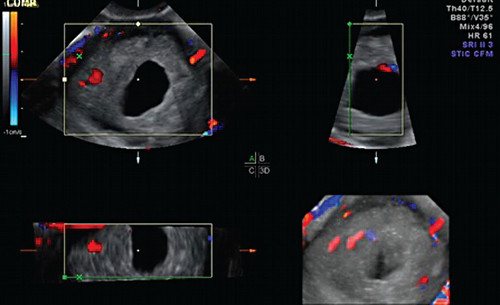

Локусы при цдк что это

Локусы при цдк что это 112 фото